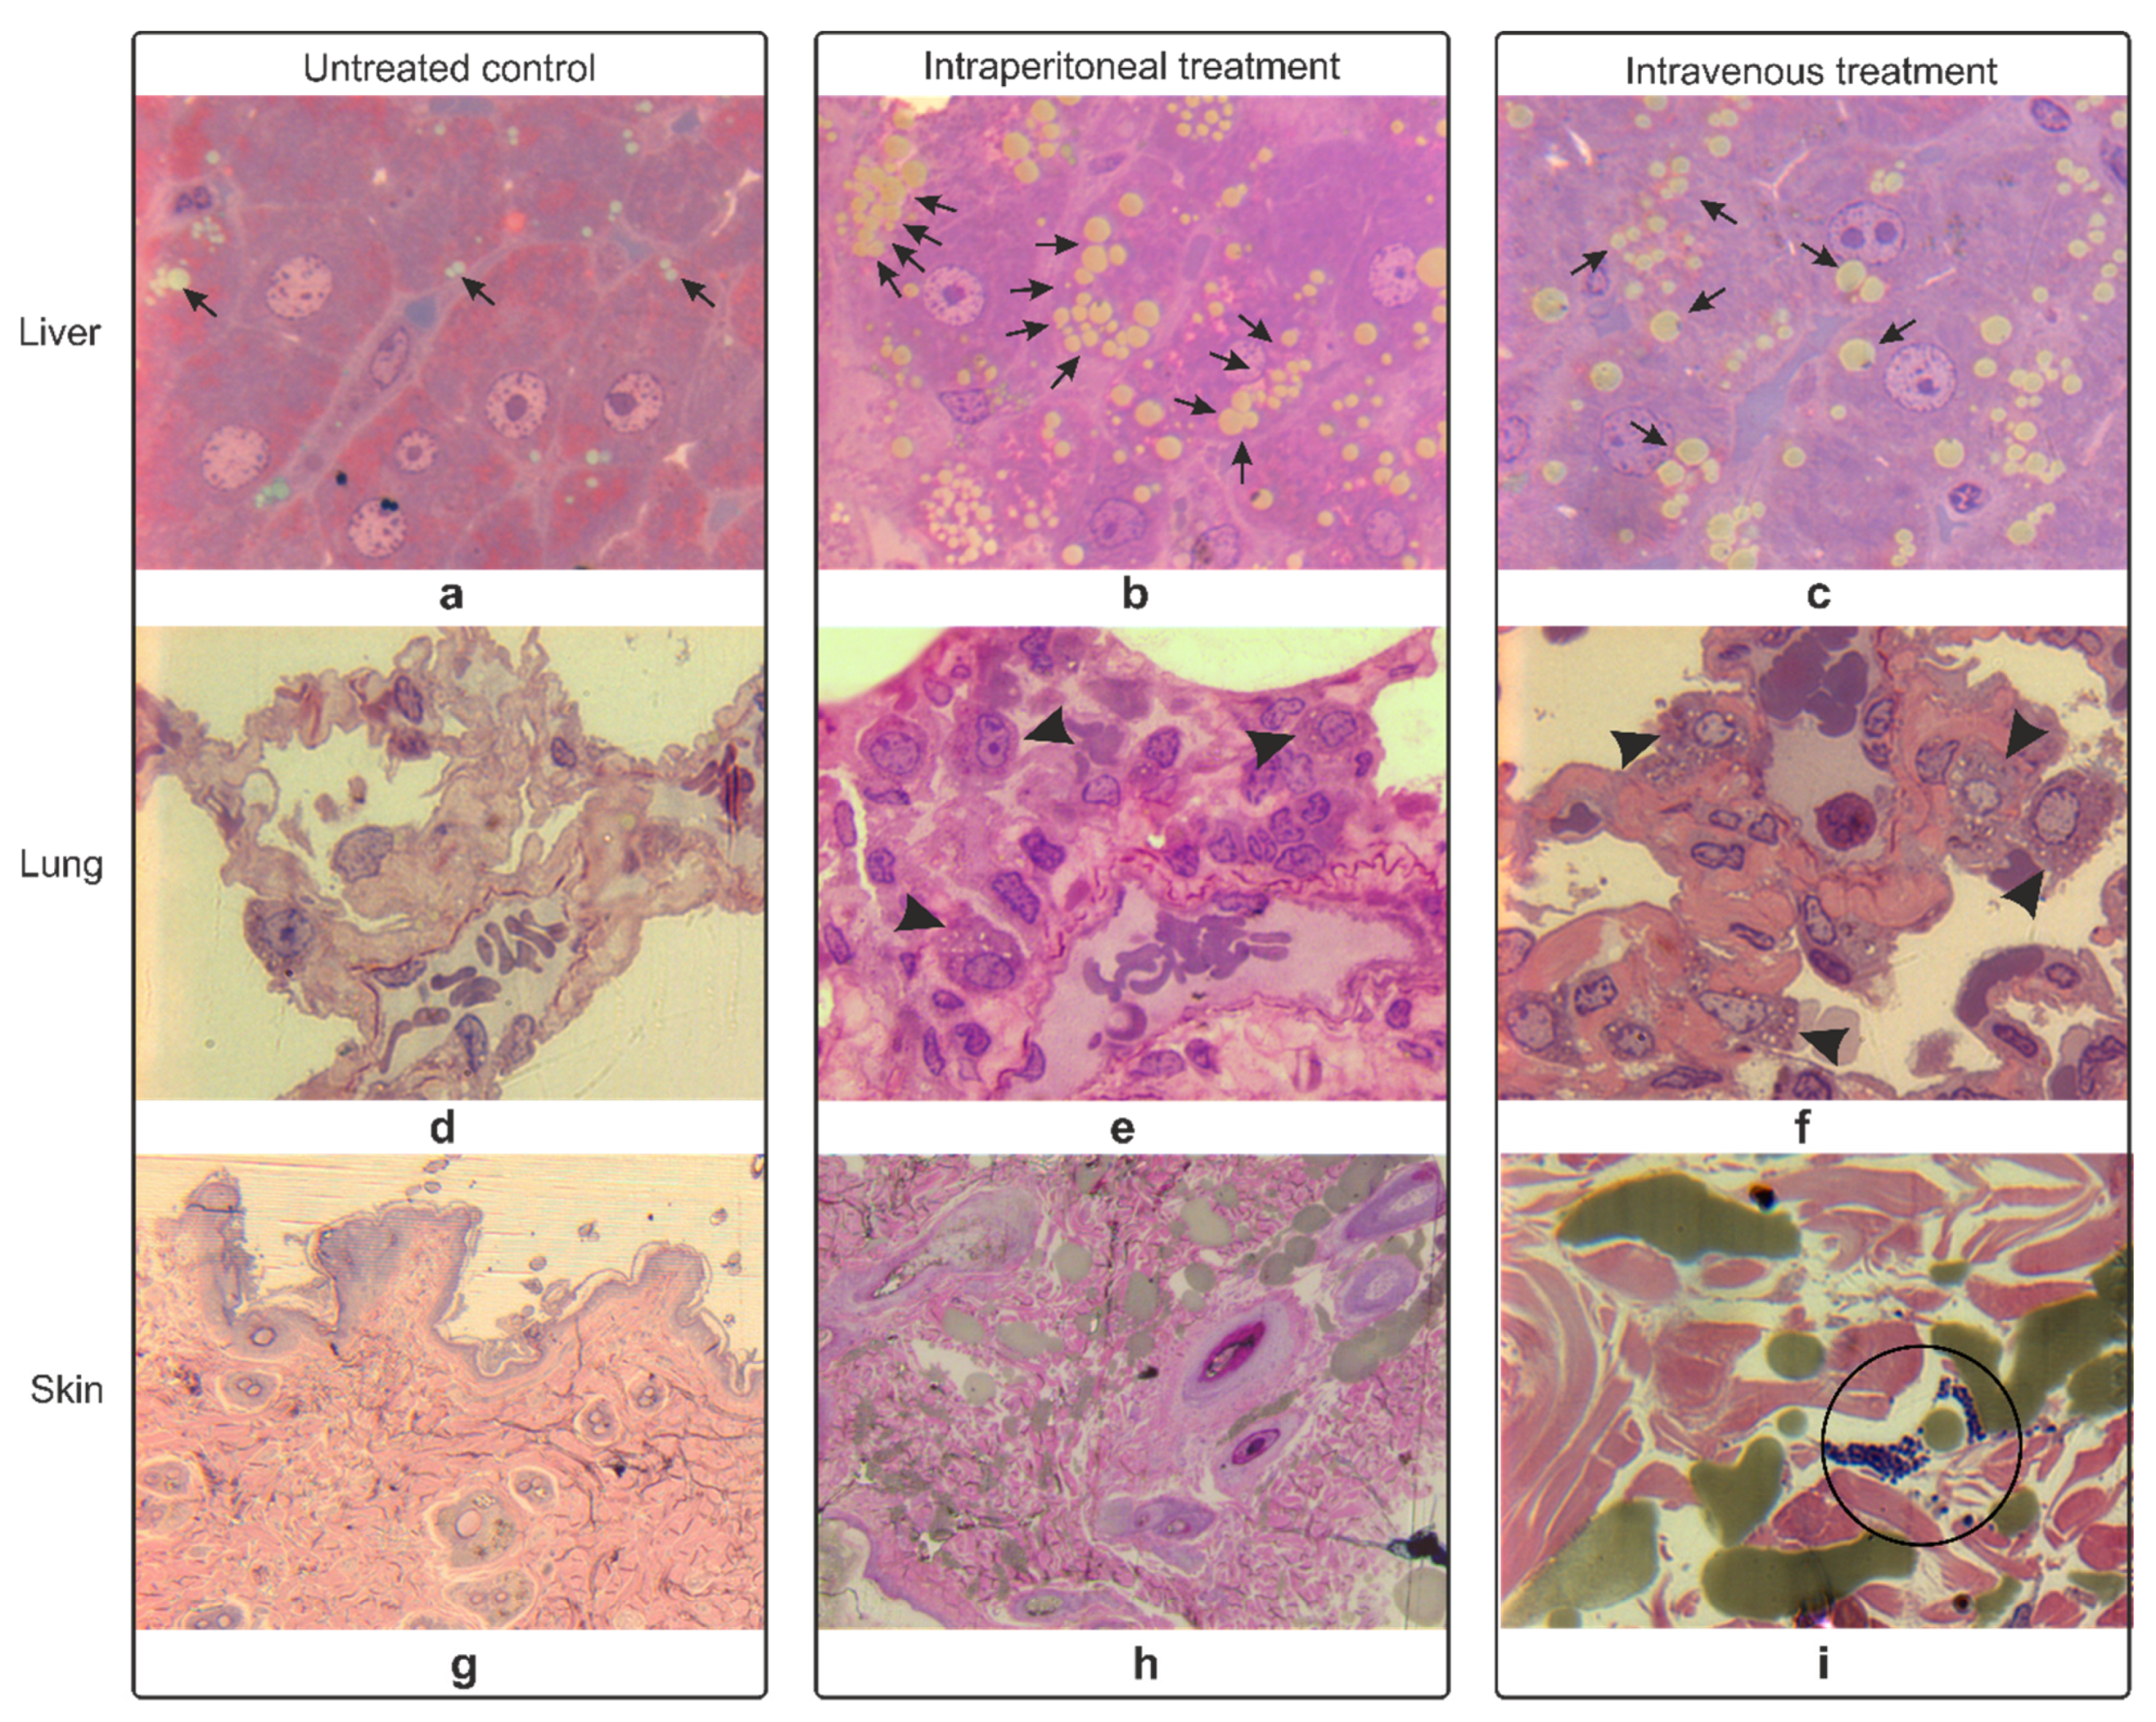

3.4. Histopathology Studies of Rat Organs

3.4.1. Hematoxylin-Eosin Staining

3.4.2. Epoxy Tissue Staining